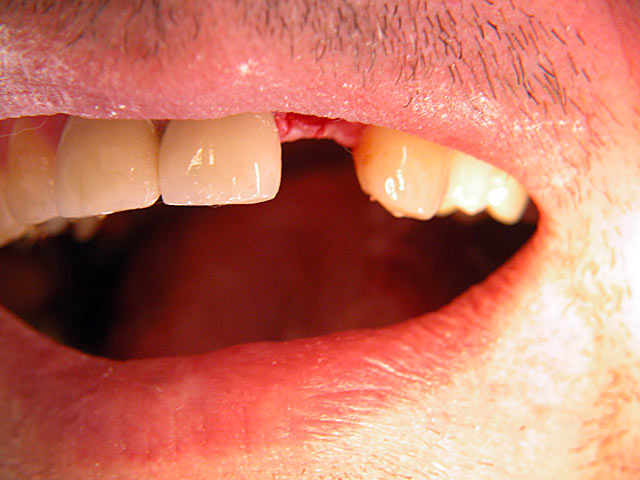

Implantation mit fester Brücke: